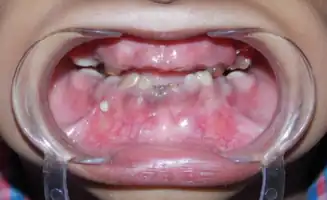

Mandibular Prognathism Development Pattern in Tricho Dento Osseous Syndrome

Shows the severe underbite pattern that is a common development pattern in individuals with Tricho Dento Osseous Syndrome

In the oral cavity 100% of people diagnosed with TDO have taurodontism which is characterized by vertically enlarged pulp chambers at the expense of the roots of the teeth; the floor of the pulp chamber and furcation is moved apically down.[1] This is due to the failure of the Hertwig epithelial root sheath which maps the shape of the forming tooth roots during active differentiation. Amelogenesis imperfecta, an abnormal formation of the enamel or external layer of the crown of the tooth, may also be present where the tooth enamel may be thin or absent. There are several clinical subsets of amelogenesis imperfecta, but common to TDO is the hypoplastic-hypomaturation subtype;[3] the hypomaturation-hypoplastic is less common in individuals with TDO. The difference between the 2 dominant subtypes is the changes seen in the enamel matrix, and the phenotypic type that predominates. The hypoplastic-hypomaturation type of amelogenesis imperfecta with TDO occurs where the tooth enamel depicts a generalized pitted pattern, with open contacts between the teeth as well as an open bite. A smaller number of cases are of the hypomaturation-hypoplastic case type, in which the enamel structure is softer due to the under maturation of ameloblasts during development. Mandibular prognathism also called a severe underbite, is also a prominent feature in TDO. Prognathism defects are diagnosed based the level of severity that this condition interferes with being able to chew or speak properly.